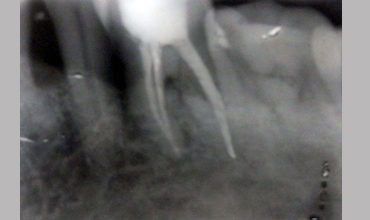

NON SURGICAL MANAGEMENT OF ENDODONTIC LESION AND SURGICAL MANAGEMENT OF PERIODONTIC LESION